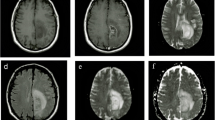

Multivoxel proton magnetic resonance spectroscopy (1H-MRS) in a case of radiation-induced necrosis of the peritumoral brain after Gamma Knife radiosurgery (GKS) of a metastatic brain tumor. Note the presence of a necrosis pattern in spectroscopic voxels containing brain tissue adjacent to the target. NAA N-acetylaspartate, Cho choline-containing compounds, Cr creatine, Lac lactate, Lip mobile lipids (Source: Chernov et al. [12])

1H-MRS showed high effectiveness for differentiating a recurrent tumor from radiation-induced necrosis. In such cases, use of a multivoxel investigation (also known as spectroscopic or chemical shift imaging) is particularly important because it provides the optimal spatial resolution required for distinguishing the coexistent viable neoplasm from treatment-induced changes [11, 49, 66]. Our study showed 100 % diagnostic accuracy of this method in cases of intracranial metastases enlarging after GKS [11]. The tumor is usually characterized by an elevated Cho peak, decreased NAA and Cr peaks, and frequent appearance of Lac and Lip peaks [10, 25, 49, 51, 84]. The two latter metabolites predominate on the spectrum of necrotic lesions, although in some of such cases no reliable peaks can be identified at all. However, in cases of early radiation-induced injury, Cho may be elevated because of inflammation, demyelination, and gliosis, and the spectroscopic pattern may resemble that of a tumor [49, 66, 84].

The list of proposed thresholds of different metabolic ratios for identifying a recurrent tumor is endless. It includes Cho/Cr >2.5 [43, 44, 51], Cho/Lip + Lac >0.3 [44], and Cho/nCho >1.2 [30] after SRS of brain metastases; and Cho/NAA >1.8 [75], Cho/Cr >1.8 [75], Cho/nCr >1.79 [68], and Lip + Lac/Cho <0.75 [68] after radiochemotherapy of intracranial gliomas. In our experience, the combination of NAA/Cho ratio <1 and Lip/Cho ratio <3 in at least one lesion-containing voxel of multivoxel 1H-MRS showed high diagnostic accuracy for identification of regrowing brain metastases after GKS, and corresponded well to the histopathology in a surgically treated cases [11, 12]. It should be kept in mind that evaluated metabolite ratios have variability of, at least, 10–15 %, whereas technical differences of processing and postprocessing during spectroscopic examinations significantly complicate comparison of results obtained on different MRI scanners. Hence, additional pattern analysis of the 1H-MR spectra can be helpful (Fig. 5).